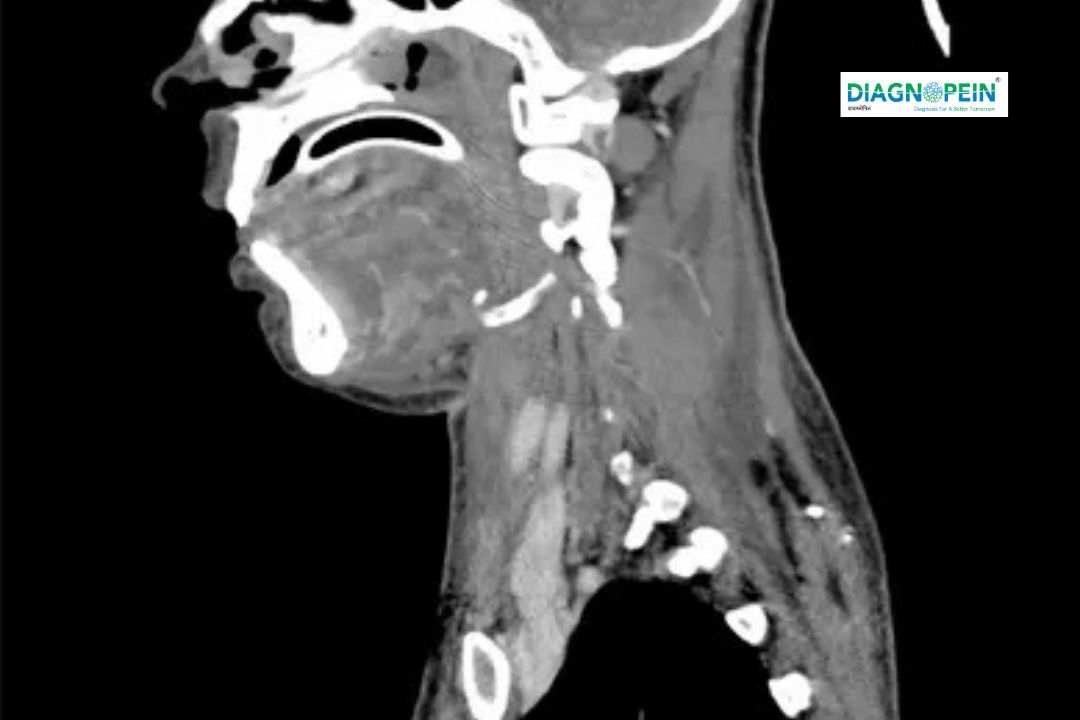

A CT Neck (Plain) scan is a detailed, non-invasive imaging test used to visualize the anatomy of the neck, including bones, soft tissues, muscles, glands, blood vessels, and the airway. This test uses multiple X-ray images taken from various angles to create cross-sectional "slices" of the neck, providing a comprehensive view of its internal structures without the need for contrast dye. It is particularly valuable for assessing cervical spine fractures, traumatic injuries, infections, tumors, lumps, swelling, and anatomical abnormalities. The procedure is quick, painless, and often used as an initial diagnostic tool due to its speed and ability to capture clear images of bone and soft tissue structures.

CT Neck (Plain) is a non-contrast computed tomography scan that captures slices of the neck area using X-rays and computer algorithms. It helps doctors assess structural abnormalities and inflammation in regions including the thyroid, lymph nodes, larynx, pharynx, and cervical spine.

Unlike CT scans performed with contrast, a plain CT only relies on natural tissue density differences, providing a reliable overview for preliminary diagnosis.